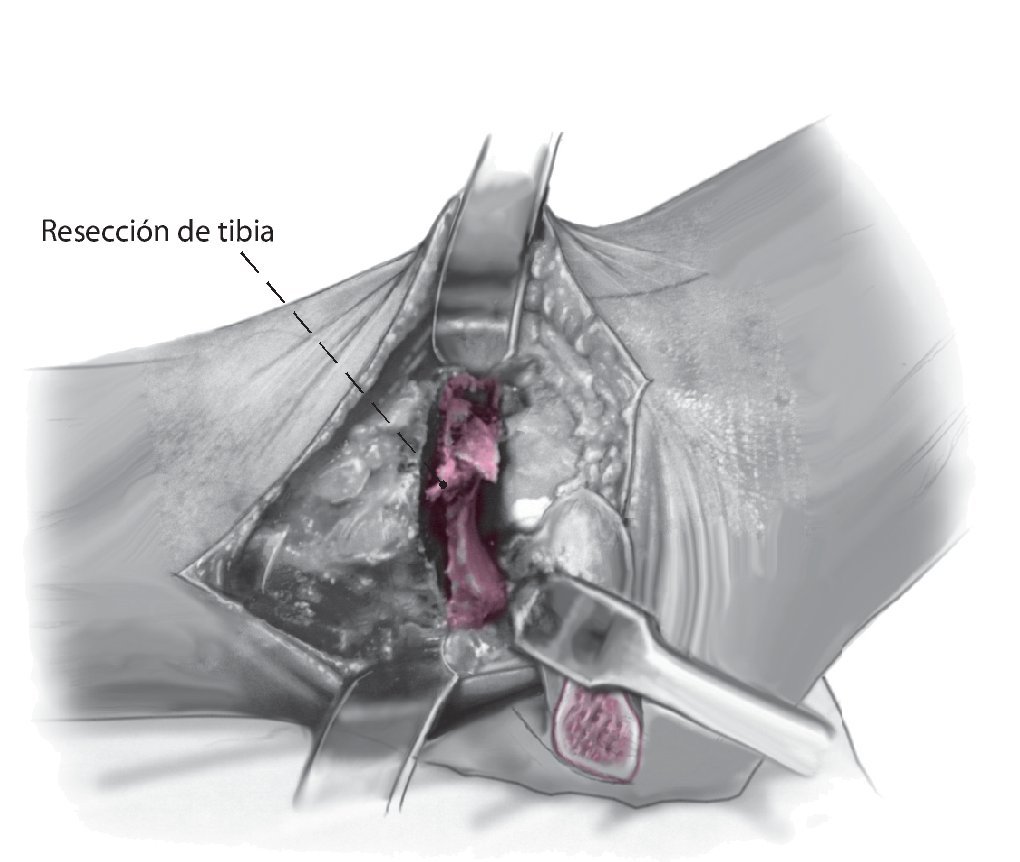

Fig. 6 Realice la osteotomía en la tibial distal perpendicular al eje tibial. Cuando se realiza de medial a lateral, el paquete neurovascular posteromedial es visible y se puede supervisar. La resección de la tibia debe ser lo menor posible para evitar el acortamiento de la extremidad.

Fig. 7 Coloque el pie en la posición deseada usando el lado contralateral como plantilla. Plantígrado con 5-8º valgo y 5-15º de rotación externa. Cuando se haya identificado la posición deseada, se realiza una osteotomía sutil de la superficie superior del astrágalo de forma exactamente paralela a la osteotomía tibial.